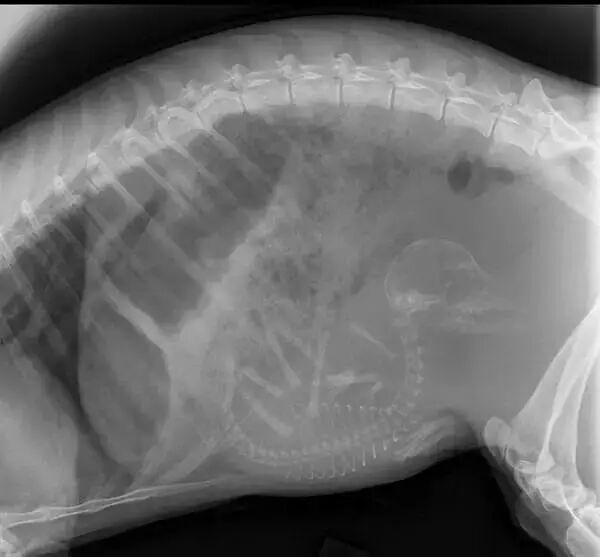

NO.3

<怀孕的猫咪>

猫咪肚子装得好乱,

强迫症好想帮它整理一下!